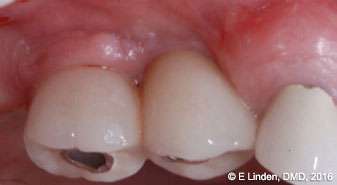

Fiberotomy: After bone sounding was complete, the modified fiberotomy procedure was performed (Figure 8). A small elevator was used to sever gingival fibers around the affected implants in order to open up the coronal aspect of the crest of gingival tissue (2 mm-4 mm deep). This step is important as it helps to introduce the laser tip into the pocket, ensuring the most efficient delivery of the laser energy to the target tissue.

Follow-up examination: The patient returned for the first follow-up examination at 1 week postoperatively (Figures 10A-10C). The healing progressed well, and no signs of swelling or inflammation were present. During follow-up examination at 6 months postoperatively, the treatment site was completely healed with no signs of periimplantitis (Figures 11A-11C). The pocket depth, measured during the 6-month postoperative visit, was reduced to 3 mm-4 mm. (Significant improvement in comparison with the initial probing depths of up to 9 mm.)